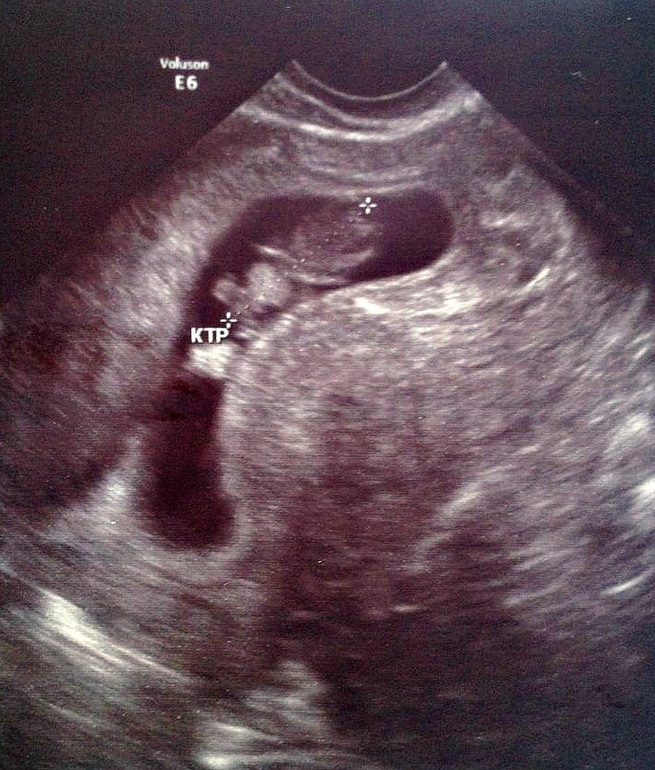

И правда у всех пя больше а нам впритык прям. Будто с 9 недель не выросло

В 9 нед ктр 19,6

В 12 нед ктр 50мм

ойНе написала ПЯДа просто все малыши так плавают там а моему вон впритык

Видела:)) как тянется... Просто у всех девочек малышу свободнее. Пространство есть. У нас будто впритык